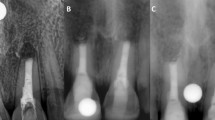

Aims Periapical lesions have been implicated in mandibular trigeminal sensory neuropathy. This study aimed to report on a case series of consecutive patients presenting with mandibular division trigeminal nerve injuries (TNI) caused by periapical lesions. Common presenting characteristics and possible strategies for management were also investigated.

Materials and methods A retrospective study of 22 patients with TNI caused by periapical lesions. Data were extracted from patient records and analysed using Microsoft Excel and SPSS. Factors associated with TNI resolution were assessed using Student's t-Tests and one-way Analysis of Variance (ANOVA), where P <0.05 indicated statistical significance.

Results Twenty-one patients had inferior alveolar nerve injuries (IANI) and one had a lingual nerve injury (LNI). The most commonly affected teeth were the first molars (11 patients; 50%). TNI symptoms included numbness, pain and/or paraesthesia. IANI resolved completely among five patients within a mean time of 4.7 months (range 1.5–12 months). Patients who showed complete resolution had the affected teeth extracted or primary endodontic treatment with antibiotics.

Conclusions Patients with TNI caused by periapical lesions can suffer significantly from combined numbness, pain and paraesthesia. Resolution of these injuries may be maximised upon early diagnosis and treatment of the periapical lesion by tooth extraction or primary endodontic treatment.